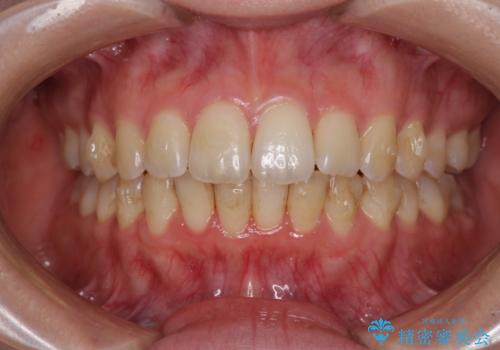

前歯のデコボコを解消 インビザラインによる矯正治療

- 上下前歯のデコボコと深い咬み合わせを気にして来院された患者様です。

インビザラインによる上下歯列の拡大と、IPR(歯と歯の間を削る)にるスペースの獲得により、前歯のデコボコを改善することとしました。

上の前歯をもう少し整えたかったのですが、患者様の治療を早く終了させたいという希望により、細かい叢生を残しての終了となりました。